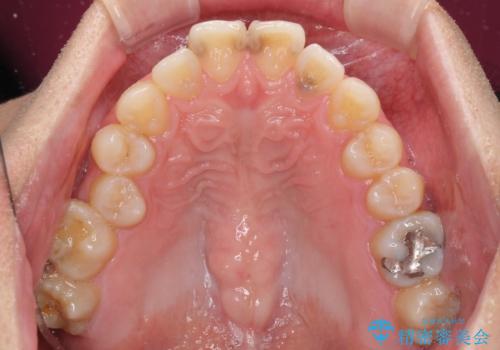

顎が左右にずれた咬み合わせ ハーフリンガルの抜歯矯正

上下の顎骨が左右に大きくずれており、奥歯が交叉咬合となっていたため、ハーフリンガルよりも表側装置をおすすめしましたが、目立たない装置を強く希望されたため、治療期間が長期化することを前提に、ハーフリンガルにて抜歯矯正を行うこととしました。

裏側装置での交叉咬合改善は非常に困難なもので、頻繁に装置の脱落がありました。